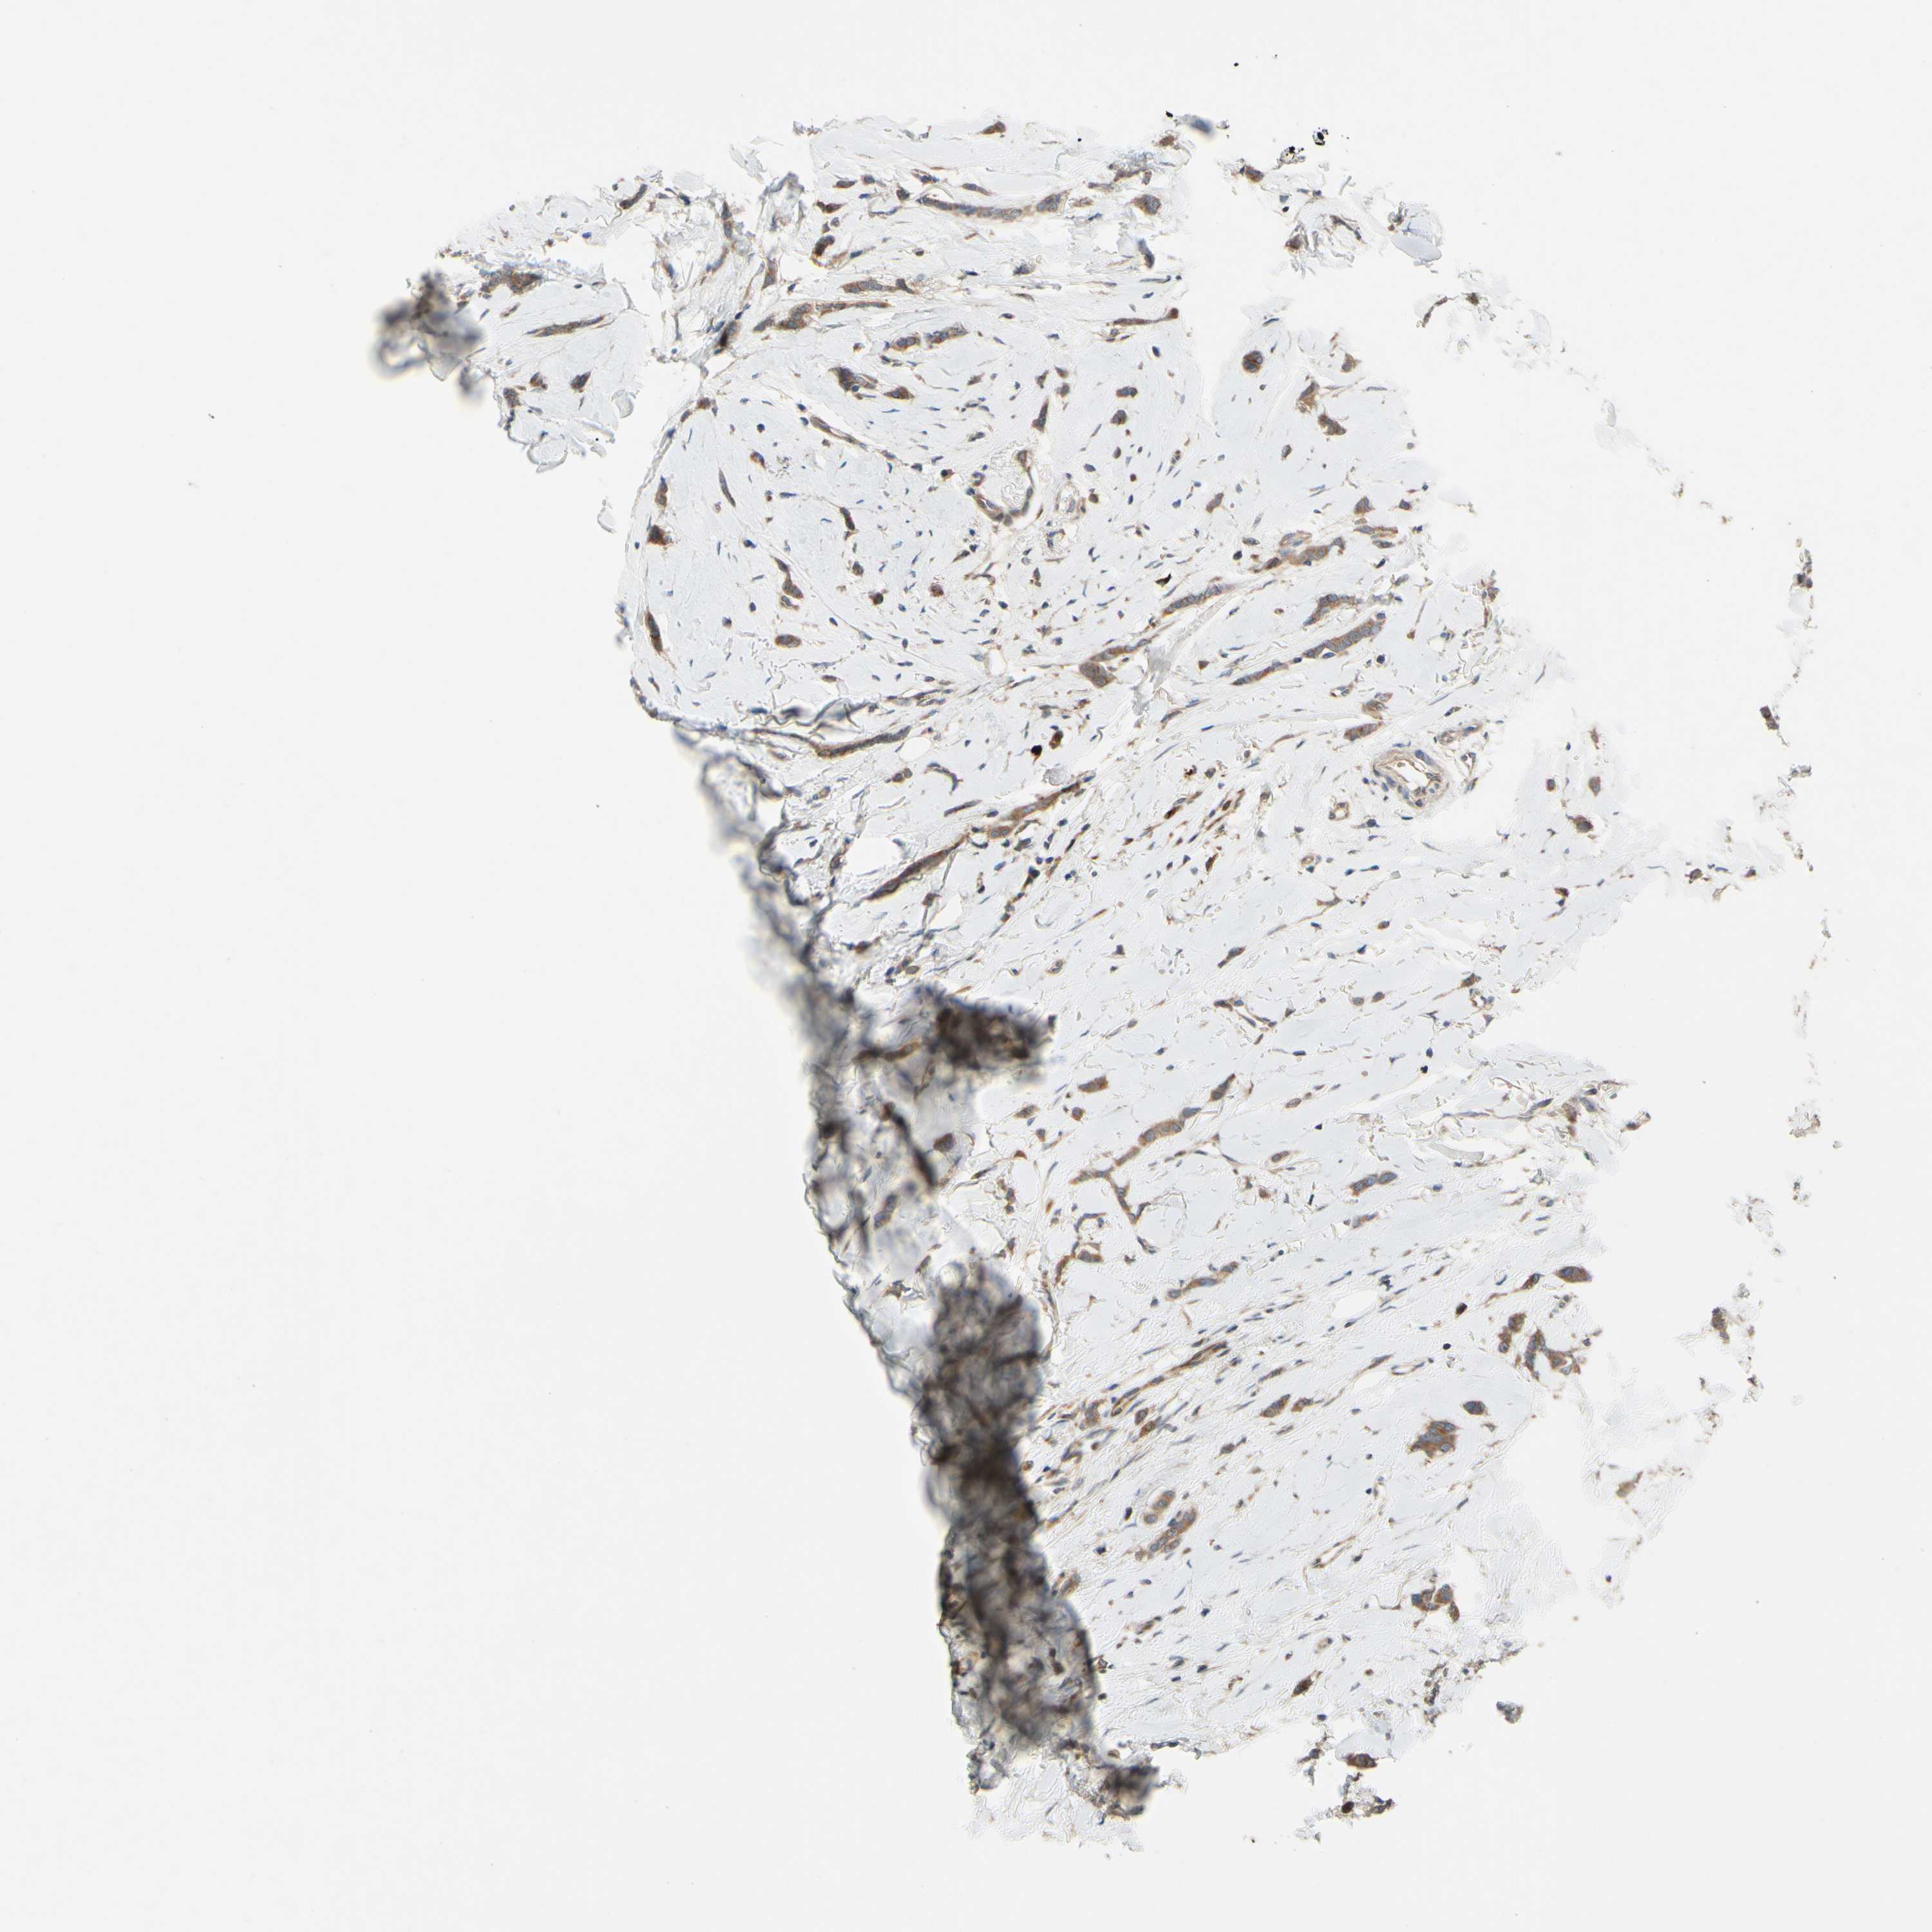

CANCER BREAST CANCER Show tissue menu

BRCA TCGA BRCA VALIDATION PROTEIN EXPRESSION

Breast cancer

Human cancer